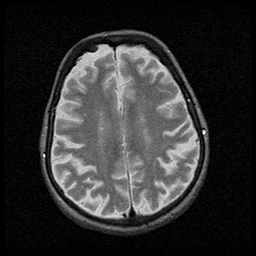

Huntington's Chorea, MR -- Slice #14

[Home][Help][Clinical] Slice 14